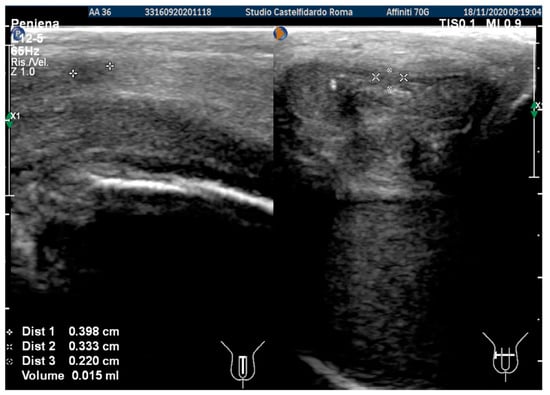

After the second treatment cycle, the IIEF score at follow-up was unchanged at 26, and we observed that the lateral-left penile curvature had an angle reduced to 20 degrees. The ultrasound showed the following dimensions: 3.98 × 3.33 × 2.20 mm (15 mm3 = volume) (Figure 3).

Figure 3. Ultrasonography of the penis after the 2nd therapy cycle (longitudinal and axial views).